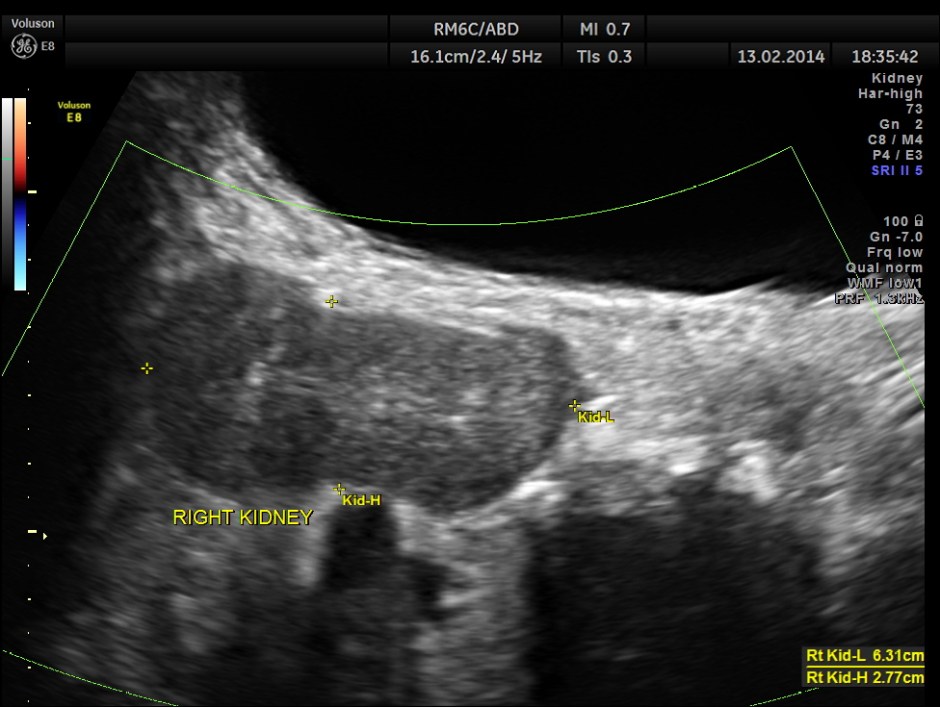

The following are the pictures of the kidney , which show the congenital horse shoe kidneys , placed ectopically in the pelvis. He had no urinary symptoms or low back ache at any time .

The right and left portions of the horse shoe are shown separately below